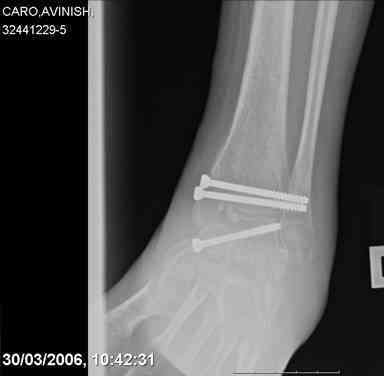

Mark, судя по снимкам в день поступления произведен А.В.Ф., а остеосинтез ч-з какое время произведен?, остеосинтез произвели открытым способом?( на снимке п/о рубцы).